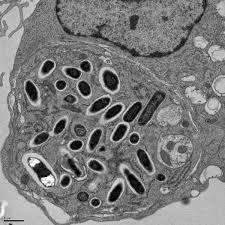

Bacillus anthracis (炭疽桿菌, G+)

- G(+)

- Spore 躲進Macrophage ,環遊世界

- Capsule: poly-D-glutamic acid

- 3 proteins

- Protective Antigen(PA83): B toxin

- Edema factor : 水腫, A toxin

- Lethal factor :致命,殺細胞,A toxin

- 2 exotoxin

- Edema toxin = PA63+EF

- Lethal toxin = PA63+LF

20不見了

Tip

- EF → cAMP

- cAMP 在腸道導致腹瀉

- EF → cAMP

- cAMP 在腸道導致腹瀉